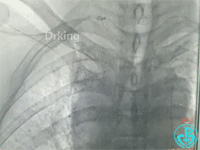

行血管造影检查结果如下:

从影像上看似乎漏口在右锁骨下与右颈动脉分叉近端。

从肱动脉置入8F鞘管,送导丝至“漏口”无法到位,导丝习惯性穿行右胸肩峰动脉中,造影发现血液外溢消失,考虑穿孔口为右胸肩峰动脉远端。接下来送入三个弹簧圈。